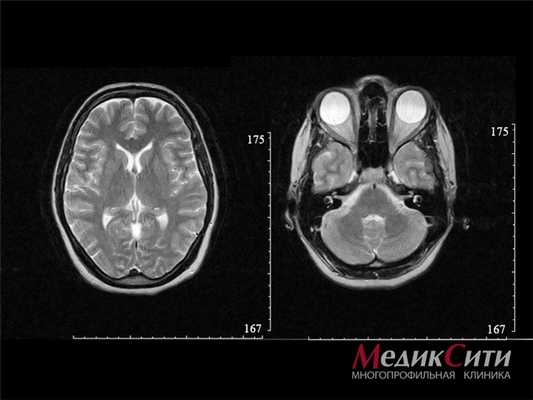

МРТ головного мозга

Для диагностики всех видов черепно-мозговых травм самыми информативными являются рентген и магнитно-резонансная томография. Это позволяют исключить перелом костей черепа.

- МРТ головы. Магнитно-резонансная томография дает возможность наиболее точно определить уровень и характер поражения оптических волокон и внутриглазных мышц, выявить локальные участки кровоизлияния.

Черепно-мозговая травма — это повреждение костей черепа и/или мягких тканей (мозговые оболочки, ткани мозга, нервы, сосуды). По характеру травмы различают закрытую и открытую, проникающую и непроникающую ЧМТ, а также сотрясение или ушиб головного мозга. Клиническая картина черепно-мозговой травмы зависит от ее характера и тяжести. Основными симптомами являются головная боль, головокружение, тошнота и рвота, потеря сознания, нарушение памяти. Ушиб головного мозга и внутримозговая гематома сопровождаются очаговыми симптомами. Диагностика черепно-мозговой травмы включает анамнестические данные, неврологический осмотр, рентгенографию черепа, КТ или МРТ головного мозга.

Всех пострадавших с черепно-мозговой травмой в обязательном порядке транспортируют в стационар, где после подтверждения диагноза устанавливают им постельным режим на срок, который зависит от клинических особенностей течения заболевания. Отсутствие признаков очаговых поражений головного мозга на КТ и МРТ головного мозга, а также состояние пациента, позволяющее воздержаться от активного медикаментозного лечения, позволяют решить вопрос в пользу выписки пациента на амбулаторное лечение.

Методом выбора при диагностике ушиба головного мозга является КТ головного мозга. На КТ определяют ограниченную зону пониженной плотности, возможны переломы костей свода черепа, субарахноидальное кровоизлияние. При ушибе мозга средней степени тяжести на КТ или спиральной КТ в большинстве случаев выявляют очаговые изменения (некомпактно расположенные зоны пониженной плотности с небольшими участками повышенной плотности).

Обязательным методом обследования пострадавших с черепно-мозговой травмой является компьютерная томография. Относительными противопоказаниями к ее проведению могут служить геморрагический или травматический шок, а также нестабильная гемодинамика. С помощью КТ определяют патологический очаг и его расположение, количество и объем гипер- и гиподенсивных зон, положение и степень смещения срединных структур головного мозга, состояние и степень повреждения головного мозга и черепа.